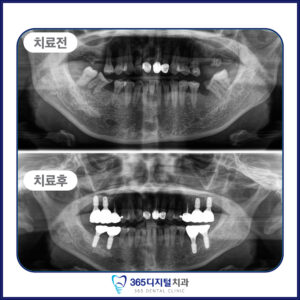

임플란트는 단순히 인공치아를 심는 것이 아닌,

환자의 삶의 질을 회복하는 진료라고 생각합니다.

계획된 진단과 세밀한 설계,

그리고 환자 개인의 구강 구조에

맞춘 접근이 중요합니다.

– 뼈이식이 필요한 복잡한 케이스를 정밀하게 진행하고 싶은 분